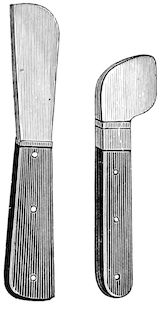

Fig. 1.—Rachitis in a young goat.